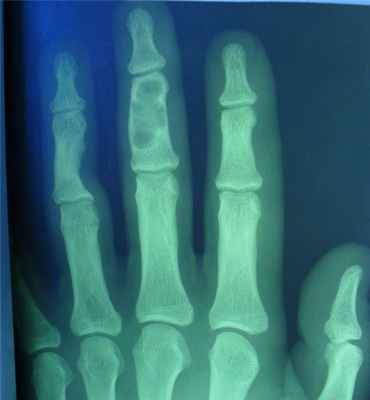

- поражаются фаланги, пястные, плюсневые, реже запястные кости, отростки позвонков, передние концы верхних ребер, тазовый скелет, грудина и весьма редко – длинные трубчатые периферические кости,

- в малых цилиндрических костях хондромы гнездятся в диафизах и эпифизах, в больших трубчатых – только в метафизарных костях,

- как правило хрящевые опухоли множественны и чаще всего наблюдаются в числе одного или нескольких на фалангах рук и пястных костях,

- чаще процесс двусторонний, но не симметричный.

- опухоли шарообразны или овальны, расположены то центрально и вздувают кость изнутри, то эксцентрично и более поверхностно и связаны только с корковым веществом кости,

- опухоль состоит из прозрачного, хрящевого фона на котором видны островки, точечки из извести или костного вещества,

- наружные контуры гладкие и при доброкачественном течении не прерываются,

- на месте слияния опухолевых шаров костная перегородка иногда толстая, в других случаях истончена или отсутствует,

- при поражении эпифизарных хрящей приходится видеть торможение роста кости в длину или ее искривлении,

- нередко центрально расположенная хондрома осложняется патологическим переломом,

- корковый слой неравномерен и местами утолщен,

- при хондроме поверхность кости шероховата.